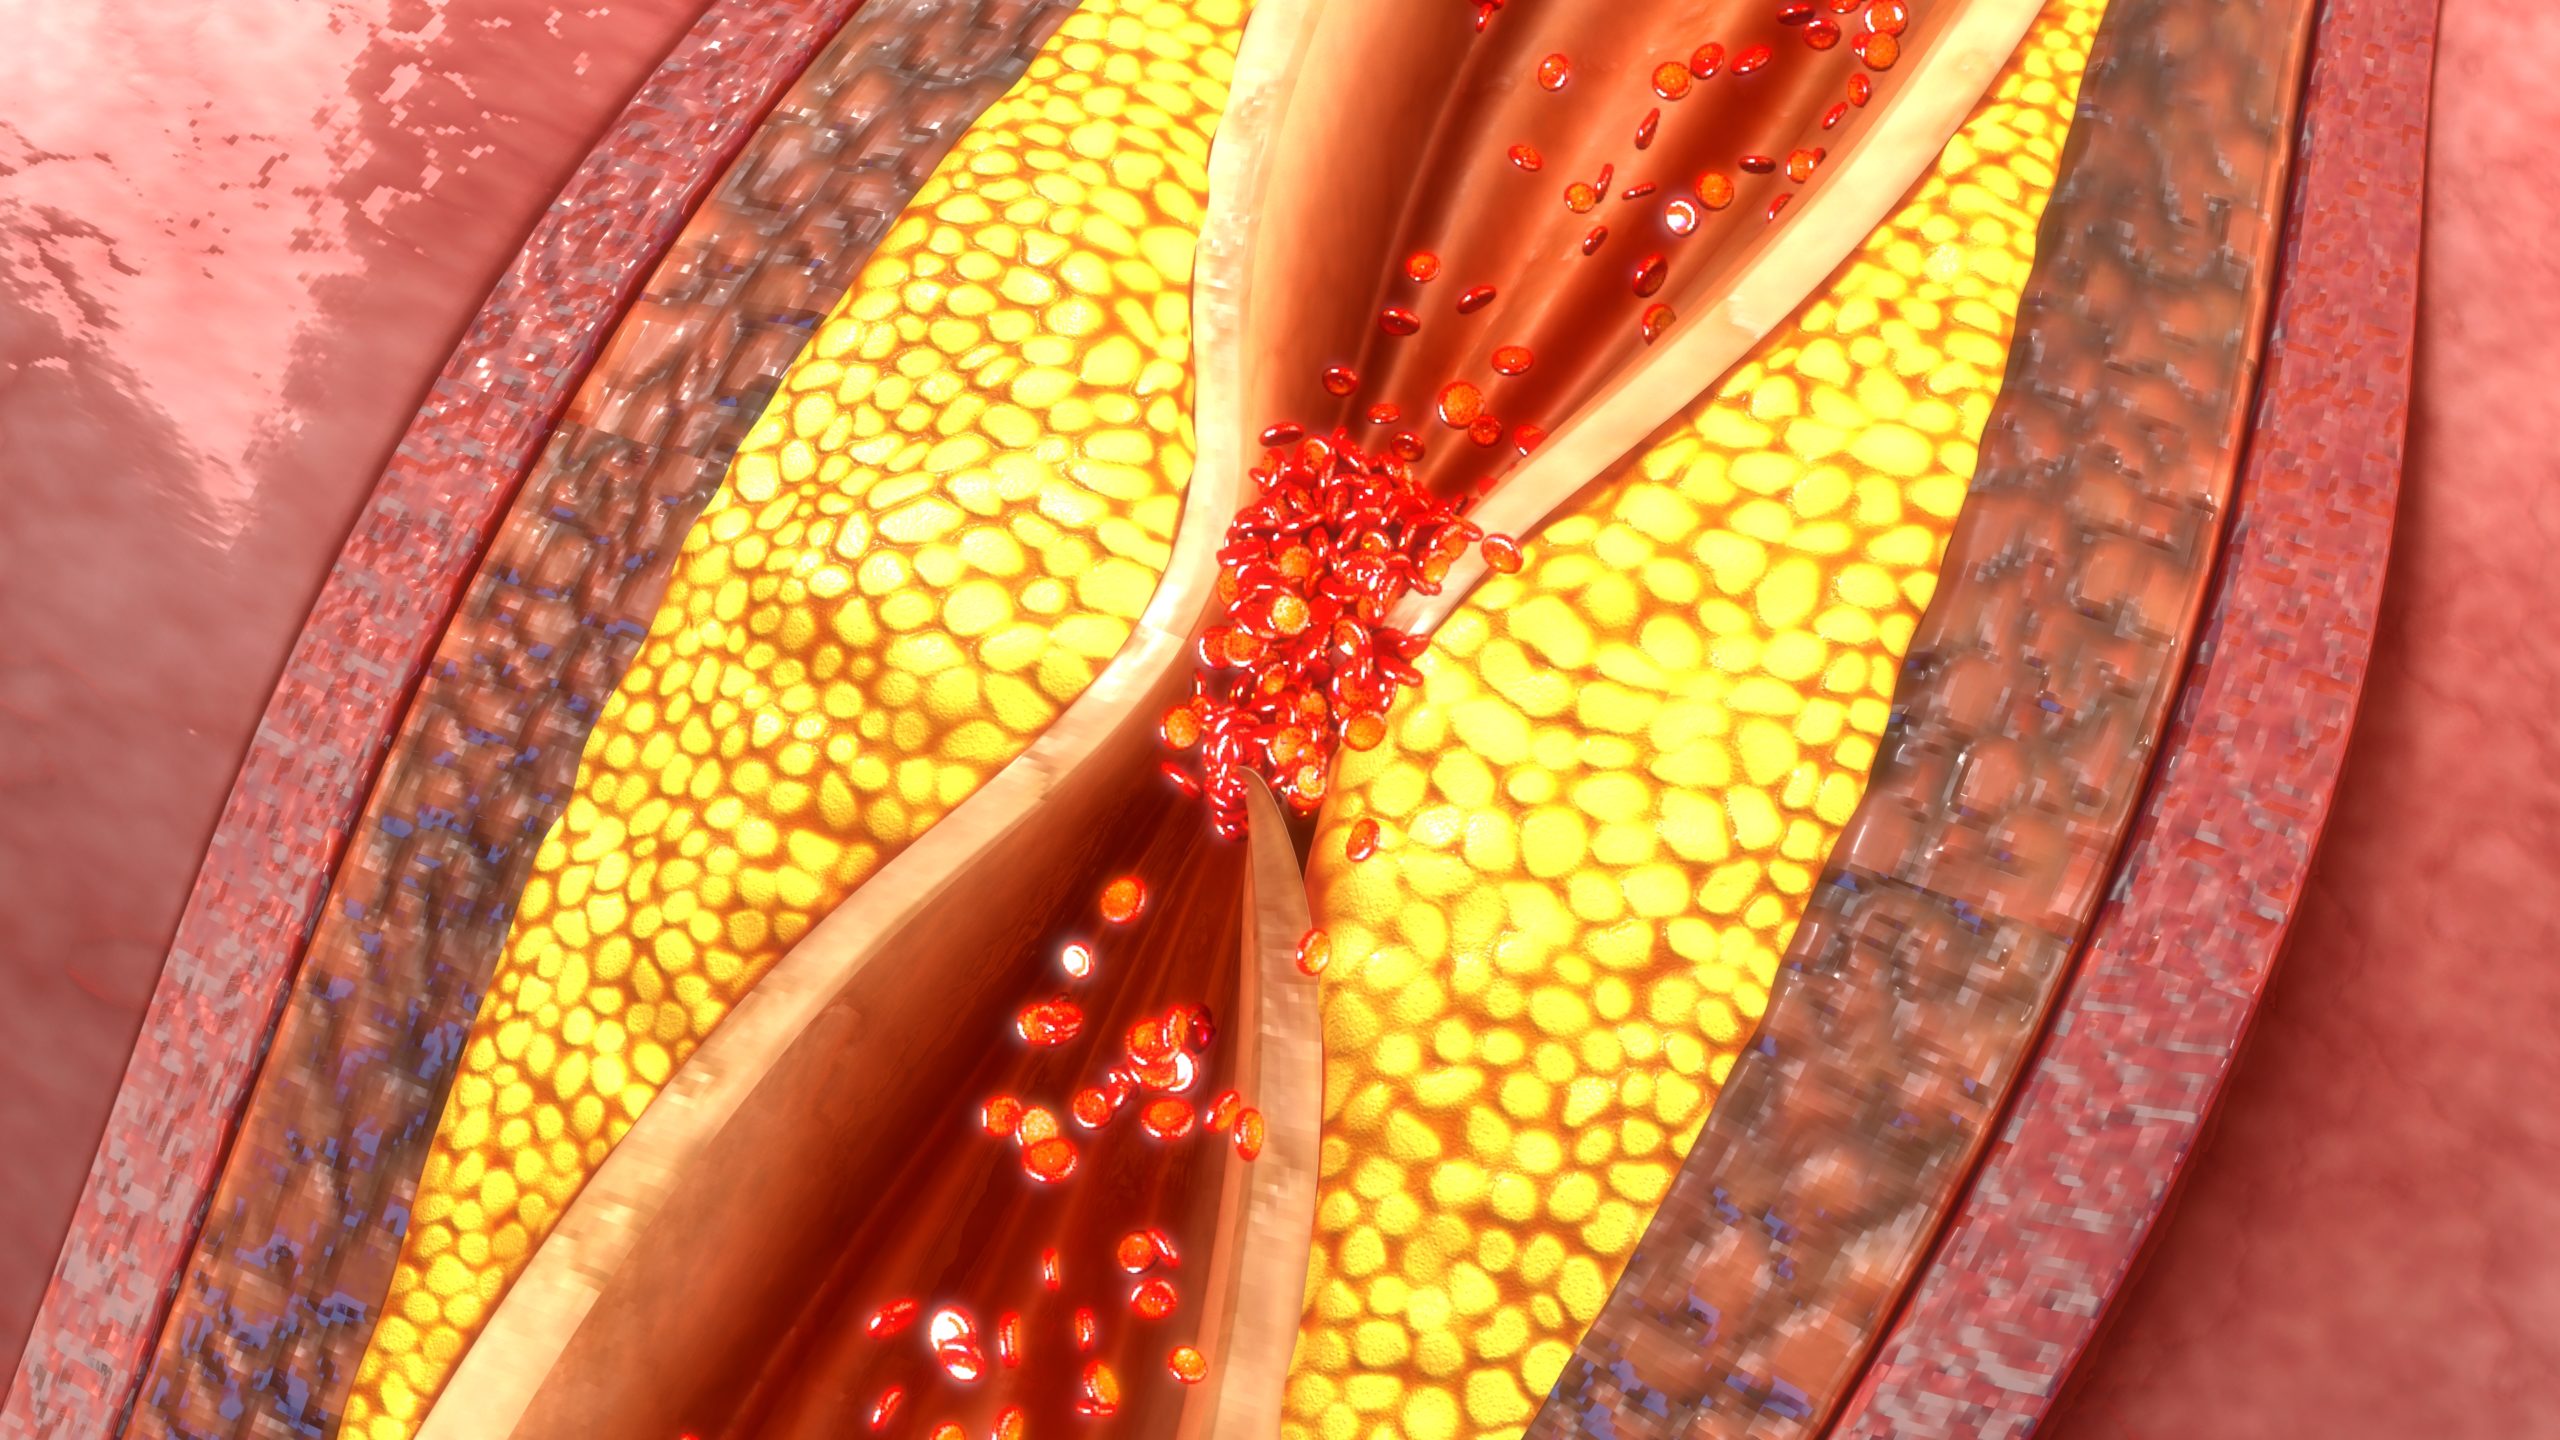

Researchers, led by Yi Qin, MD, investigated the use of the TurboHawk atherectomy in the treatment of in-stent ...